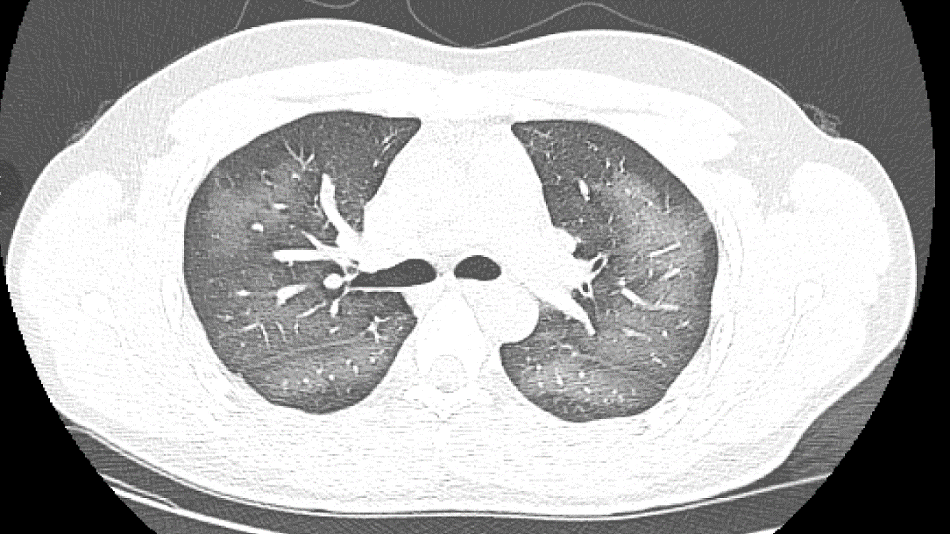

장사시의 20살 청년 리림(가명)은 외출하기 전에 자외선 차단 스프레이를 사용했는데 얼굴에 살포할 때 부주의로 코로 흡입했다. 바로 가슴이 답답해나고 기침 증세가 나타났다. 증상이 이튿날까지 계속되면서 호전을 보이지 않자 그는 급히 호남성 장사시 제3병원을 찾아 진료를 받았다. 검사 결과, 페 CT 영상에서 뚜렷한 넓은 범위의 흰색 모양 병변을 볼 수 있었고 보고서에는 “백색페증"이라는 진단이 적혀 있었다.

“백색페증”은 일반적으로 중증페염이 X선이나 CT검사에서 나타나는 것을 말하는데 환자의 페부는 넓은 흰색 상태를 보이고 흔히 호흡곤란, 호흡부전이 나타나며 엄중한 경우에는 기타 장기기능 장애도 나타난다.